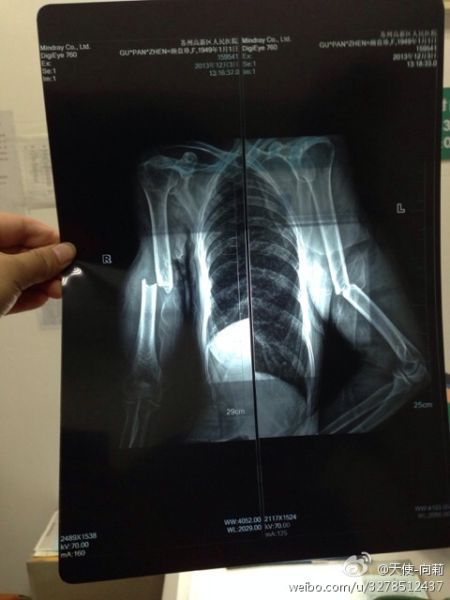

圖為微博上傳的“范木根的妻子顧盤(pán)珍手被打斷”

圖為微博上傳“范某某的妻子顧盤(pán)珍手被打斷。”

圖為微博上傳“范某某的妻子顧盤(pán)珍手被打斷?!?/font>